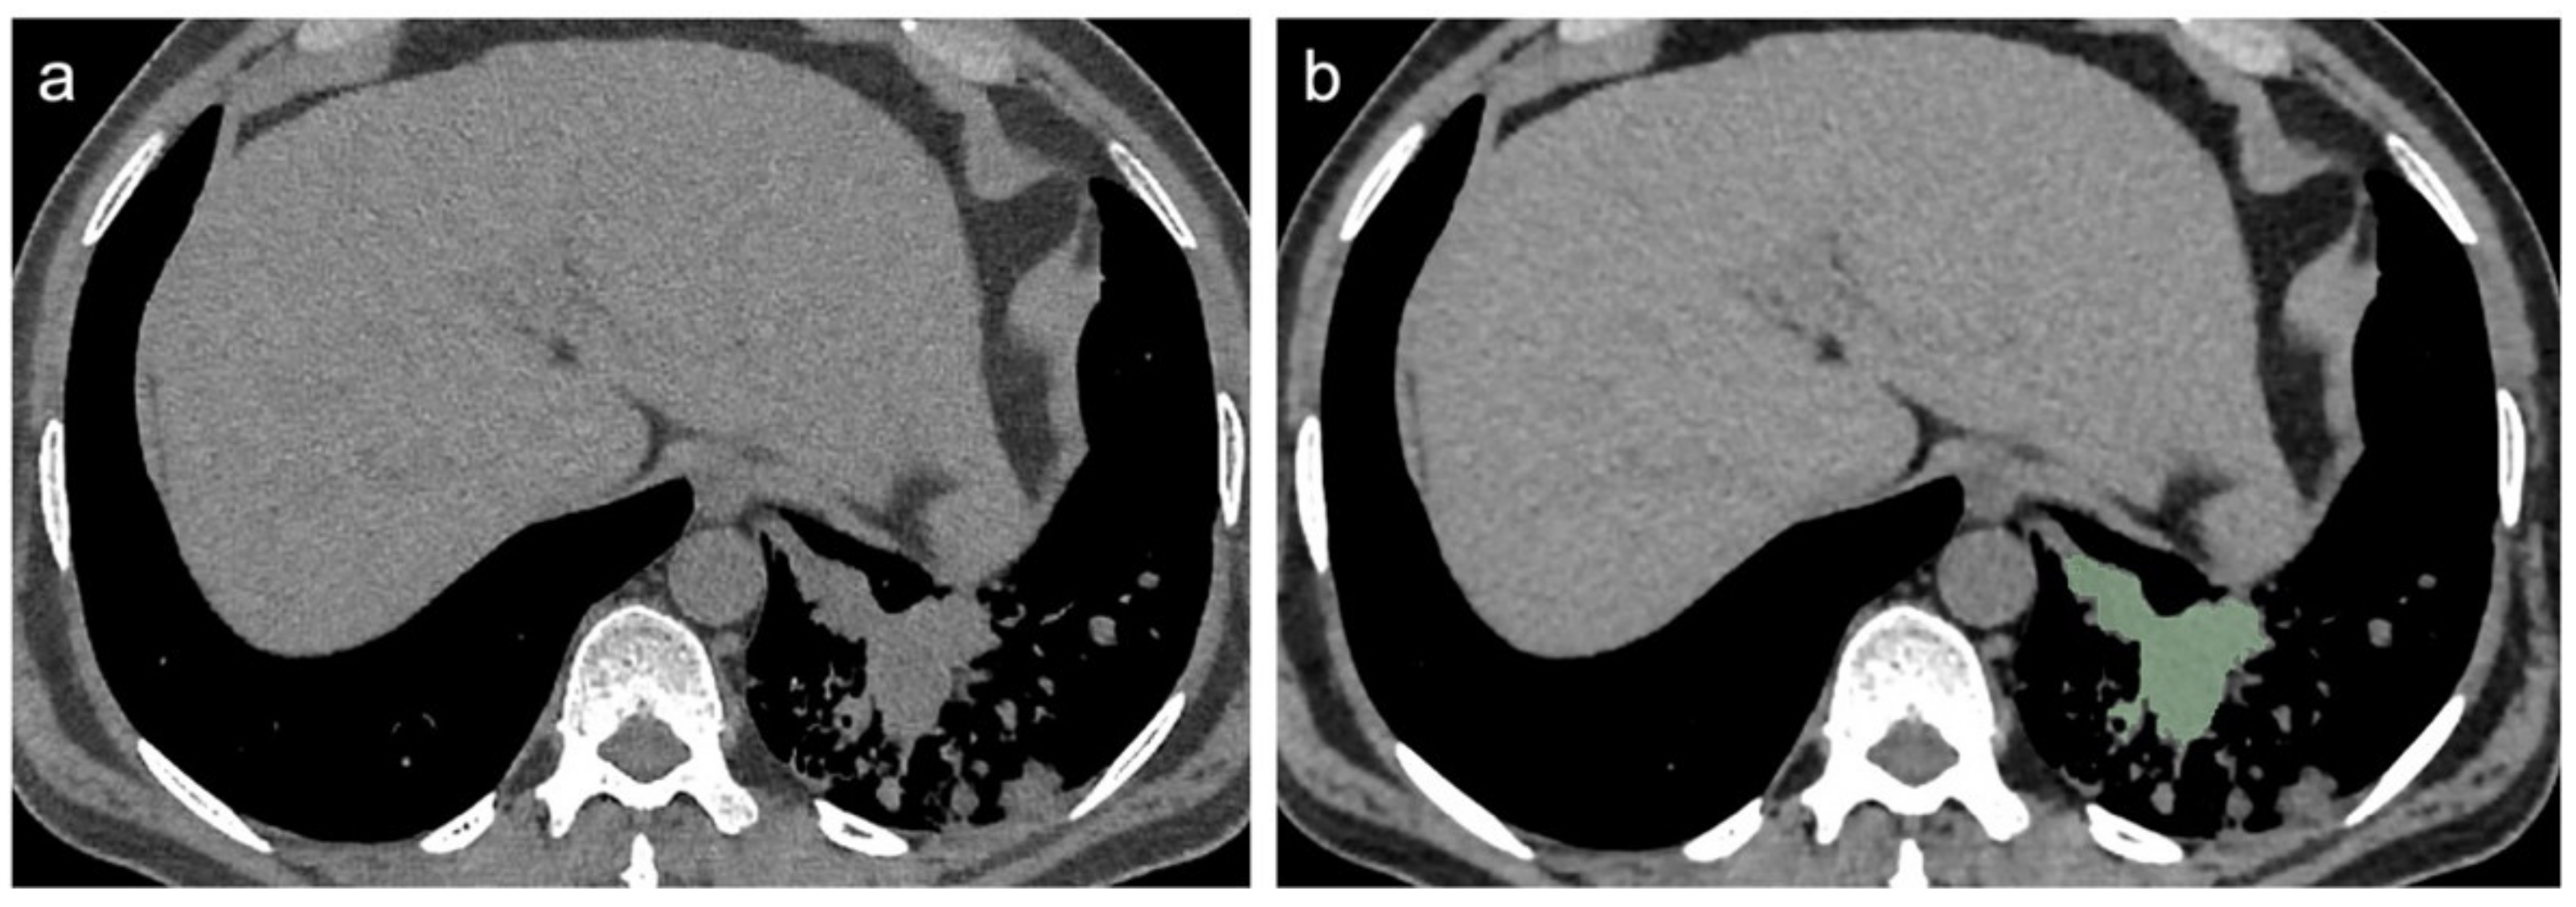

2.3. CT Scans Evaluation and Segmentation Analysis